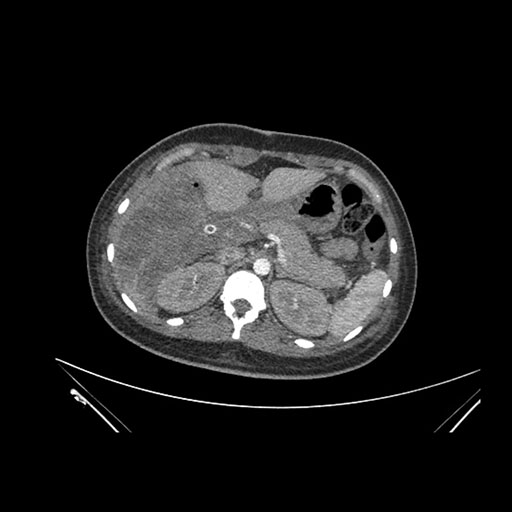

Imaging Analysis

Look through the patient's CT scan to identify any areas of concern for the necessary procedure.

Coronal Arterial

Based on initial findings, which issue(s) would you be most concerned about?